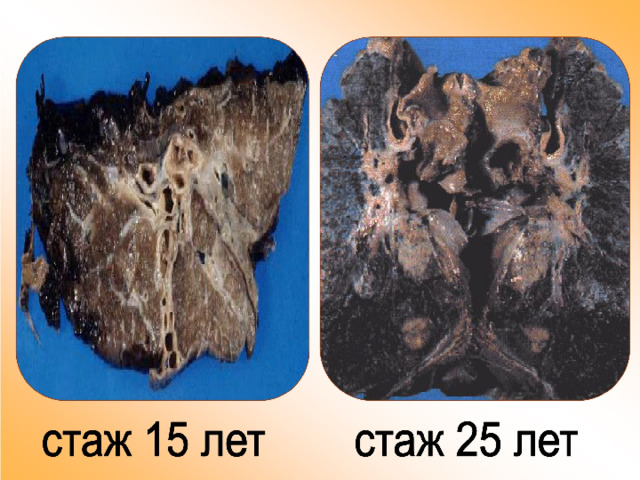

Здоровый образ жизни: Влияние курения

Раздел: Моменты озарения